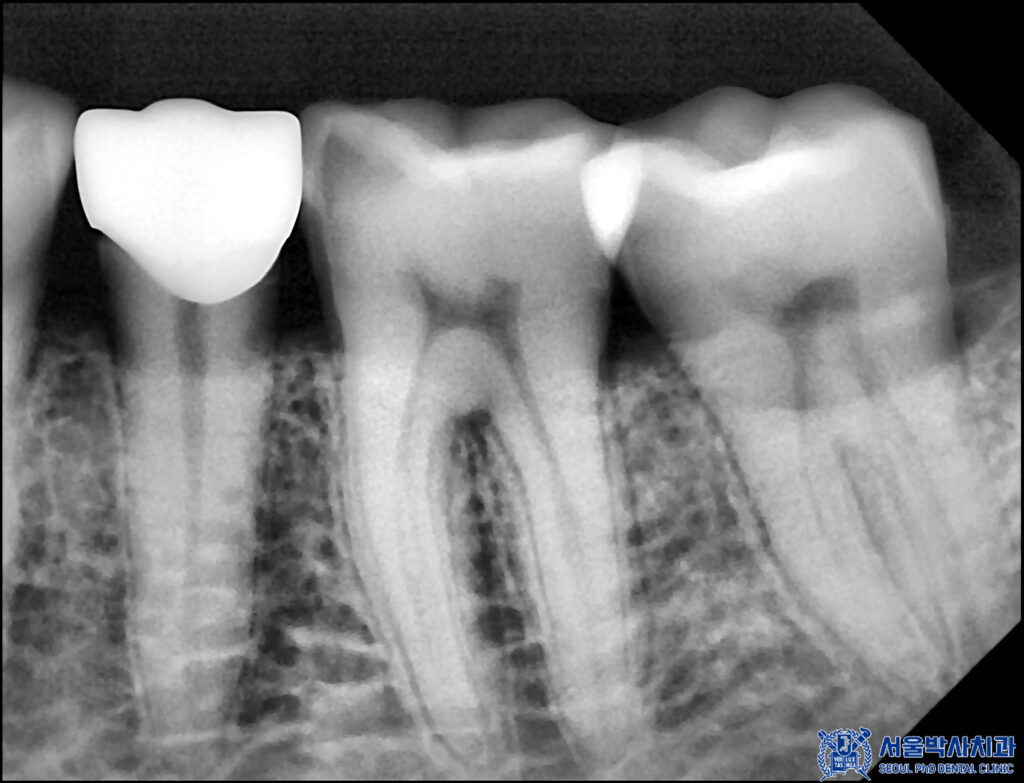

또한 왼쪽 아래 어금니도

기존 충전재와 충치를 깨끗하게 제거 후

크라운을 제작하여 세팅해 드렸습니다.

아울러 작은 어금니의 경우,

기존 충전재 아래로 충치가 확인되어

충전재와 우식 부위를 제거한 후

치아를 보호하고 기능을 회복하기 위해

크라운 치료를 진행하는 것으로

치료 계획을 수립하였습니다.